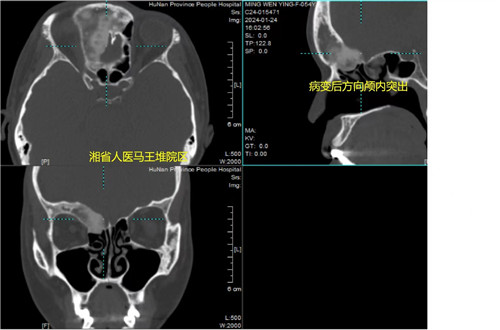

周建波主任医师仔细检查患者后发现,患者的发病位置主要在右侧前颅底和额窦,并向颅内方向突出,考虑为骨纤维异常增殖症。随着骨质增生,额窦前壁外凸会造成美容上的缺陷;病变往颅内突出及侵犯,还会压迫、侵犯脑组织,引起头痛头胀及眼胀等不适,严重影响患者的生活和工作。

“该手术的难度主要在于病变组织位于额窦和前颅底,并向眼眶外侧发展,越过了瞳孔,范围极大,在内镜下操作难度极大,并且病变与颅内组织的关系尚不明确。”周建波指出,手术成功的关键,在于术前对患者病变范围精准定位、合理的手术入路,术中手术团队密切配合,眼眶及颅内正常结构的保护,需要术者有扎实的颅底解剖知识和丰富的临床经验,术中也需要麻醉师的精细管理。